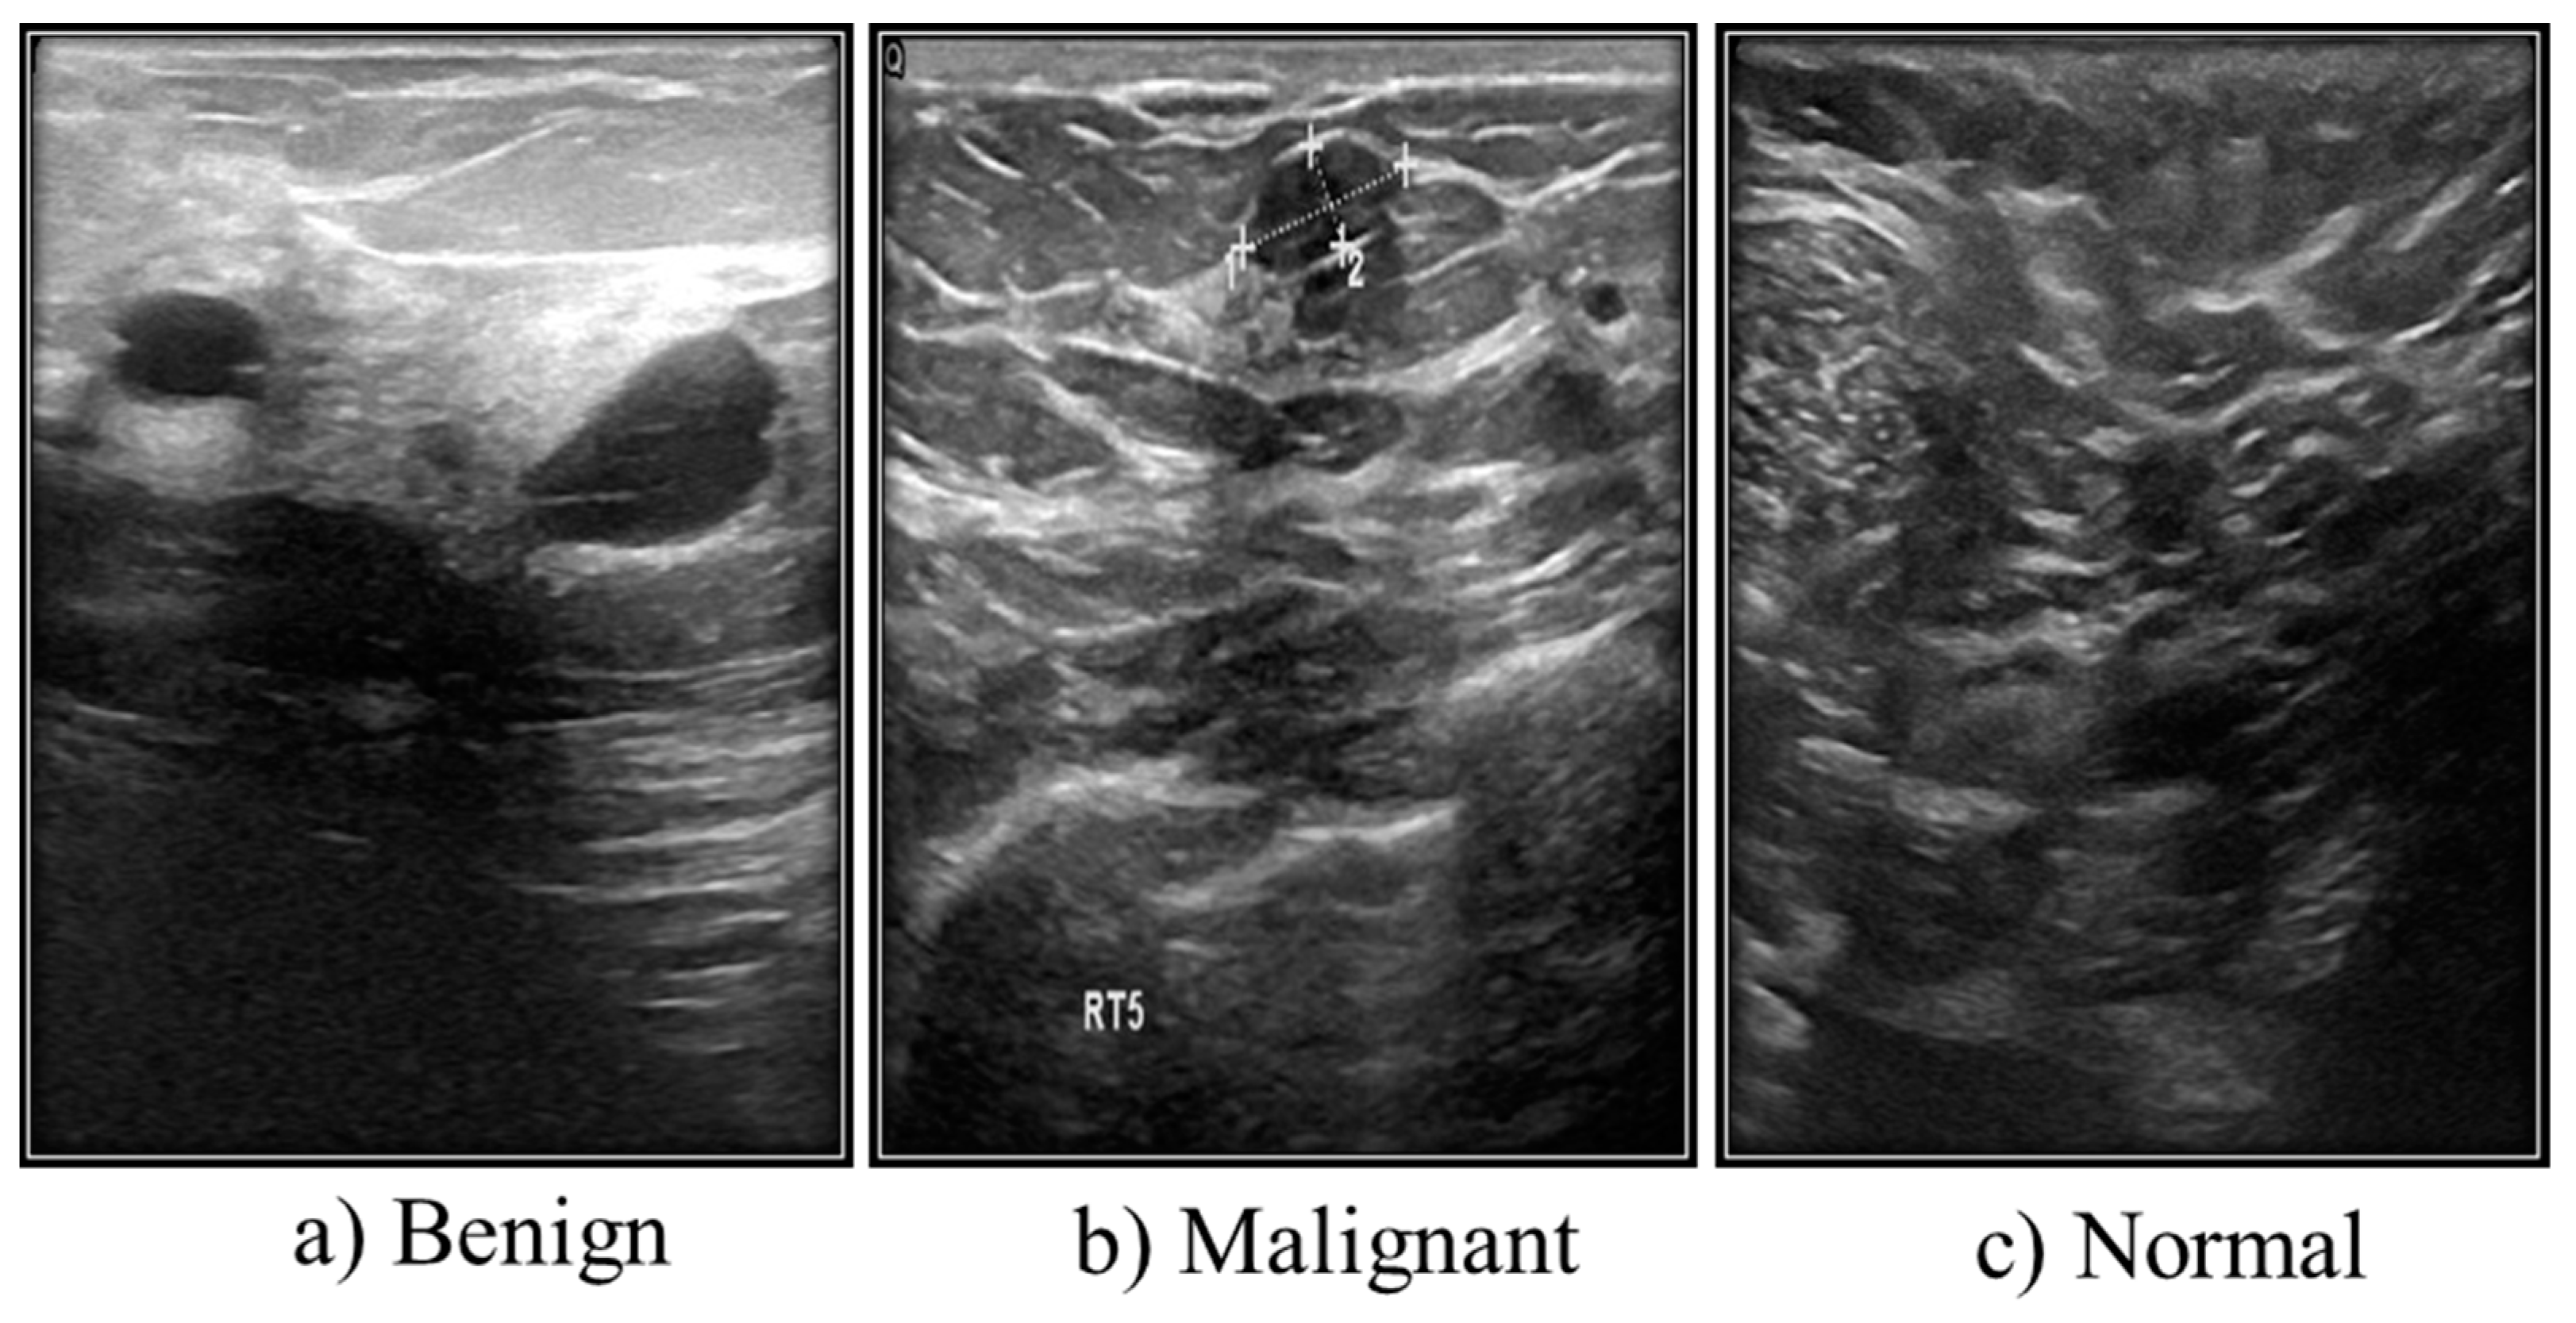

| Case | Number of Images |

|---|---|

| Benign | 487 |

| Malignant | 210 |

| Normal | 133 |

| Total | 780 |